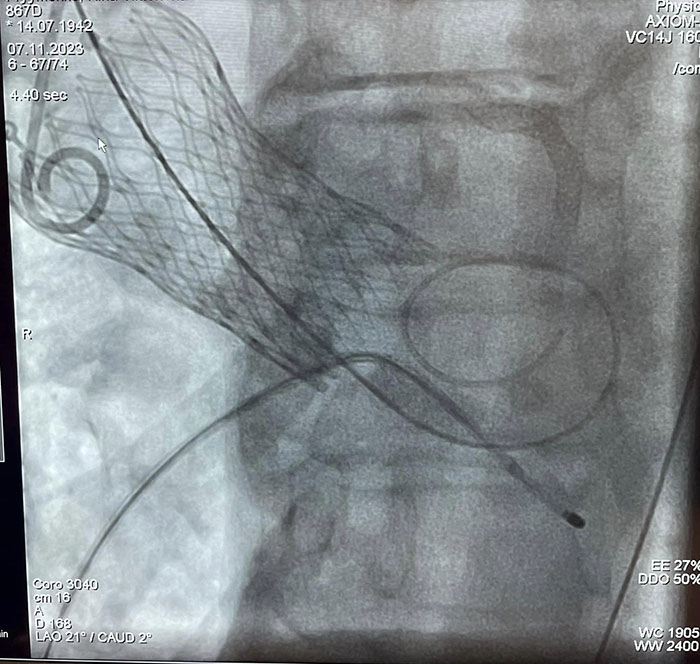

"В рамках цієї операції біологічний аортальний клапан, який закріплений на кінчику катетера, просувається до серця та закріплюється на місці аортального клапана, - йдеться у повідомленні. - Перевага: не потрібно проводити стернотомію грудної клітки, також немає потреби у використанні апарату для штучного кровообігу, немає наркозу, немає реабілітації".

Операції проводились бригадою медиків у складі Узун Д.Ю., Журавльов М.В., Бабкіна Н.А., Муравський Є.А., під прокторством Дітківського І.О. завідувача відділення: рентген-ендоваскулярних методів лікування вроджених та набутих вад НІССХ ім. М.М. Амосова.